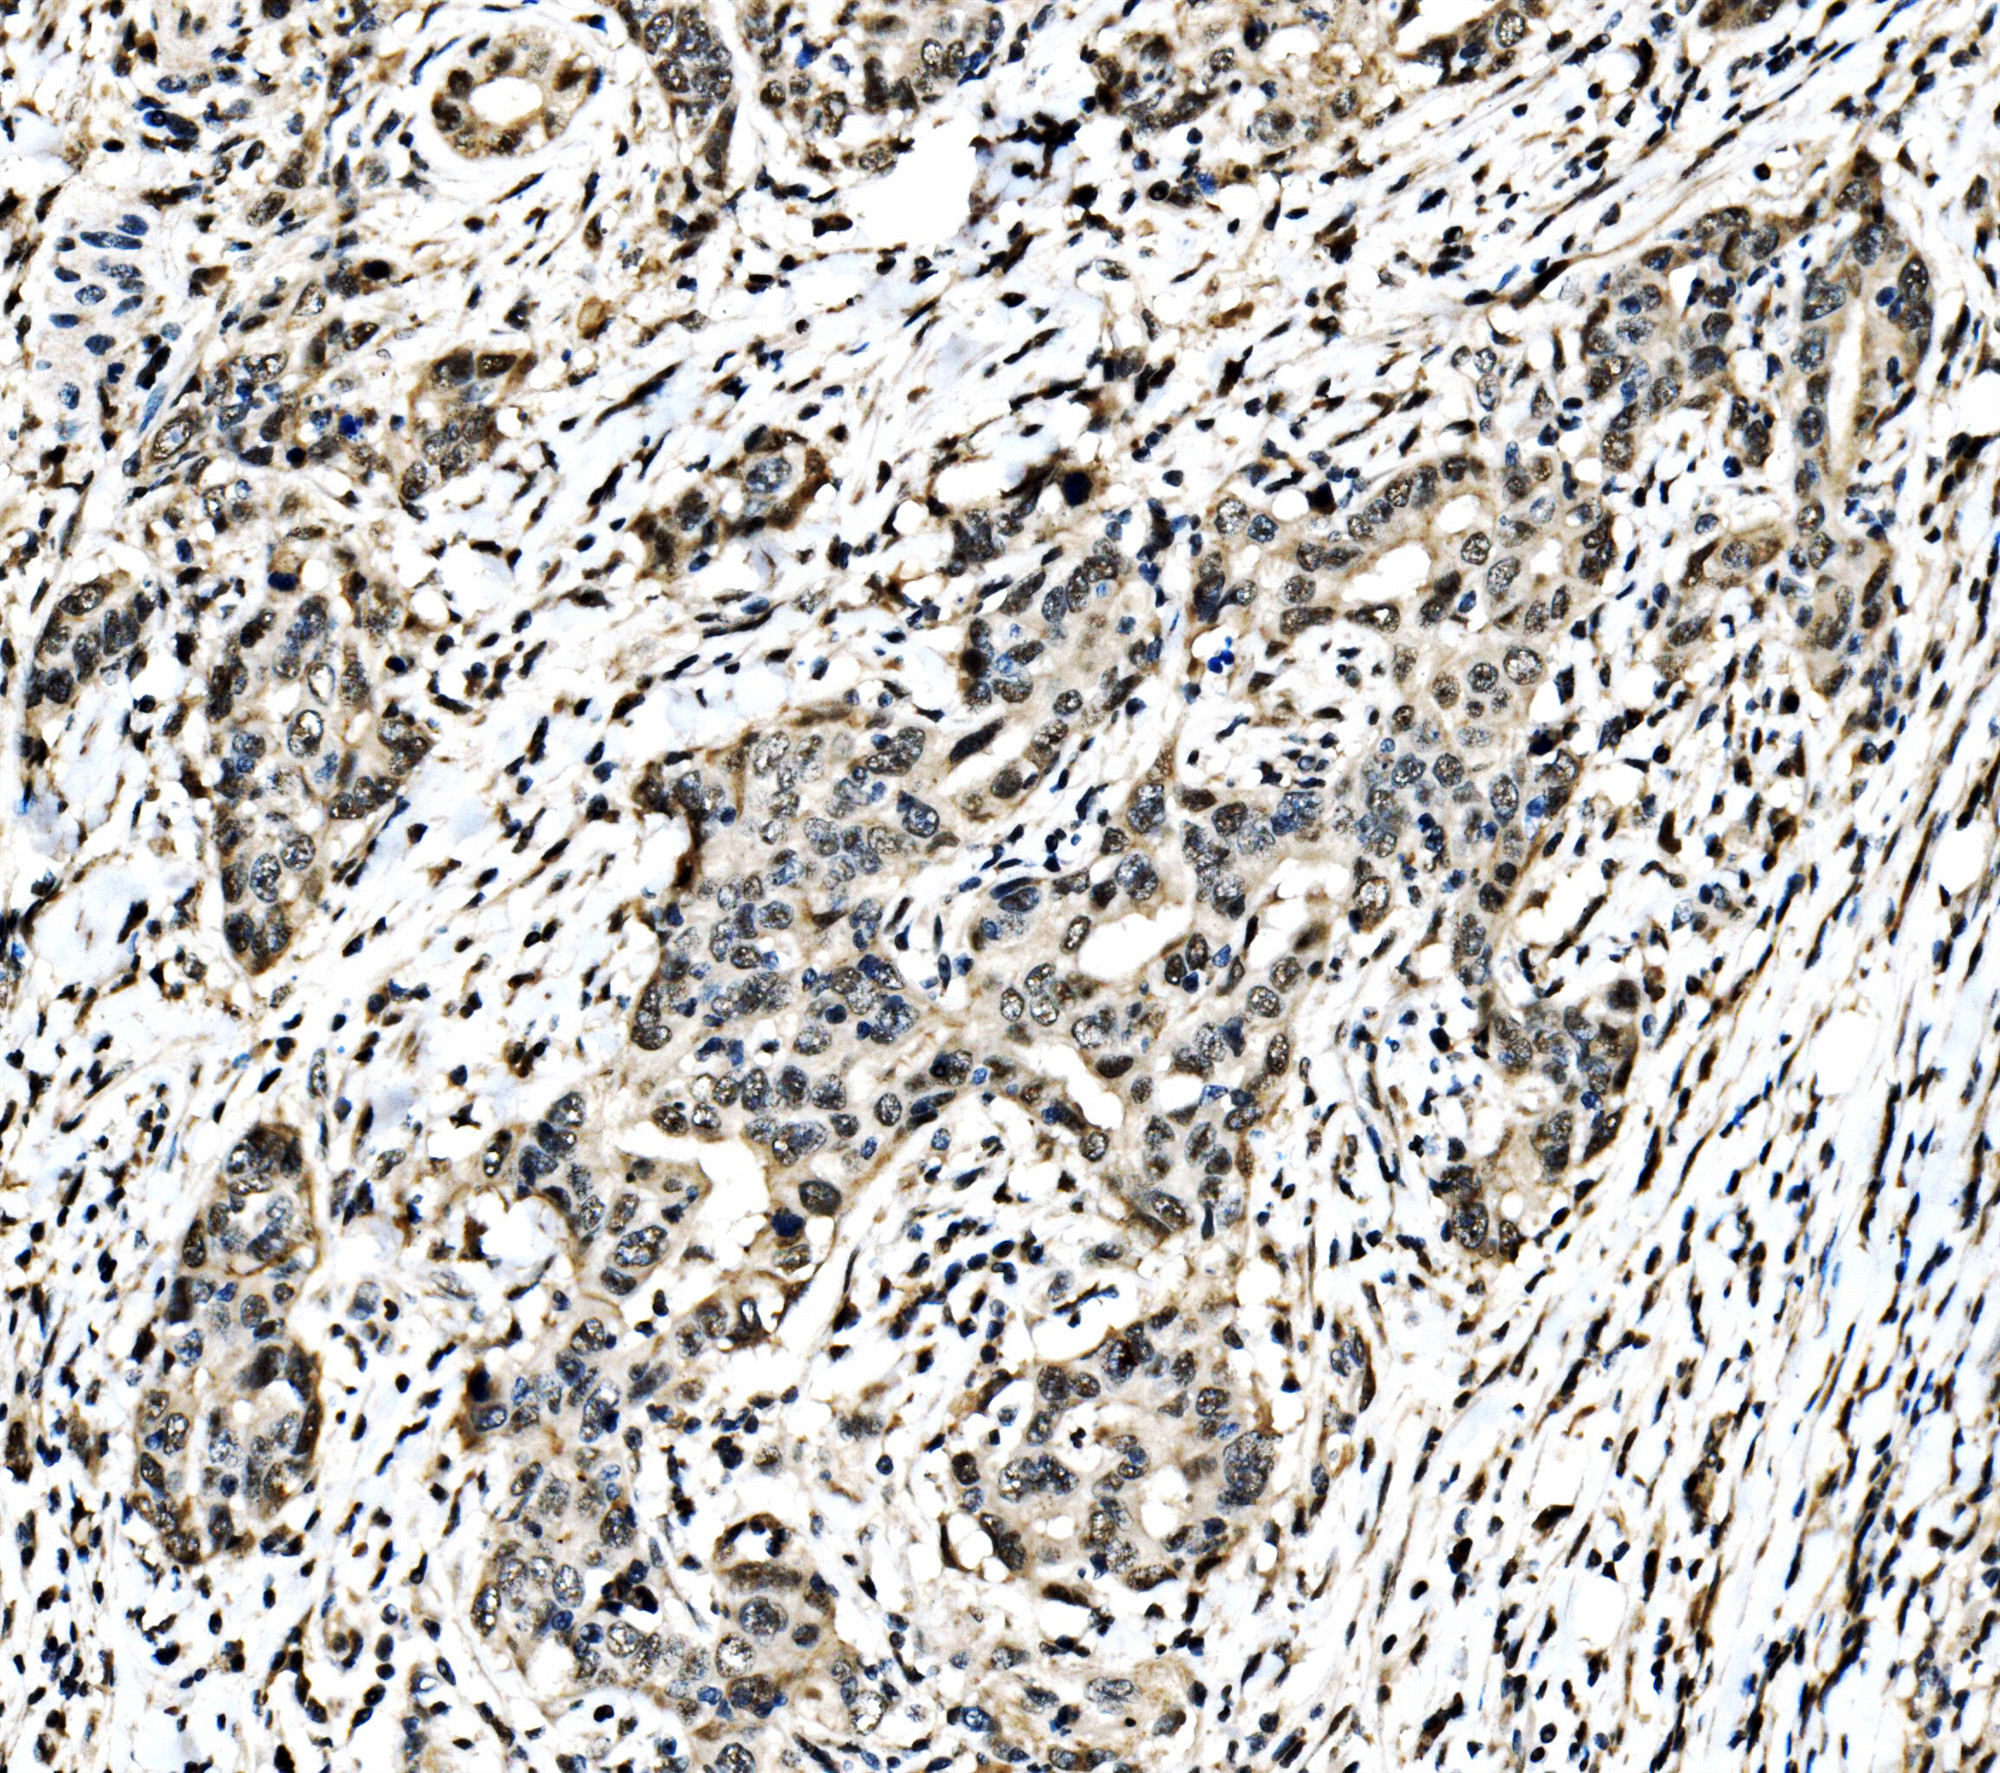

IHC analysis of c-Jun/JUN using anti-c-Jun/JUN antibody (A02038-3).

c-Jun/JUN was detected in a paraffin-embedded section of human the renal pelvis is squamous metaplasia tissue. Biotinylated goat anti-rabbit IgG was used as secondary antibody. The tissue section was incubated with rabbit anti-c-Jun/JUN Antibody (A02038-3) at a dilution of 1:200 and developed using Strepavidin-Biotin-Complex (SABC) (Catalog # SA1022) with DAB (Catalog # AR1027) as the chromogen.